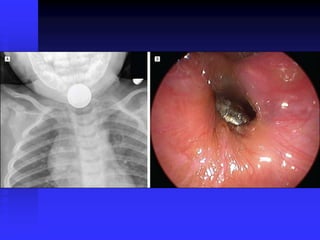

Foreign Body Airway Obstruction

FBAO

FBAO: High Risk Groups

 > 90% of deaths: children < 5 years old

 65% of deaths: infants

FBAO: Signs/Symptoms

 Suspect in any previously well, afebrile

child with sudden onset of:

Respiratory distress

Choking

Coughing

Stridor

Wheezing

FBAO: Management

 Minimize intervention if child conscious,

maintaining own airway

 100% oxygen as tolerated

 No blind sweeps of oral cavity

 Wheezing

Object in small airway

Avoid trying to dislodge in field